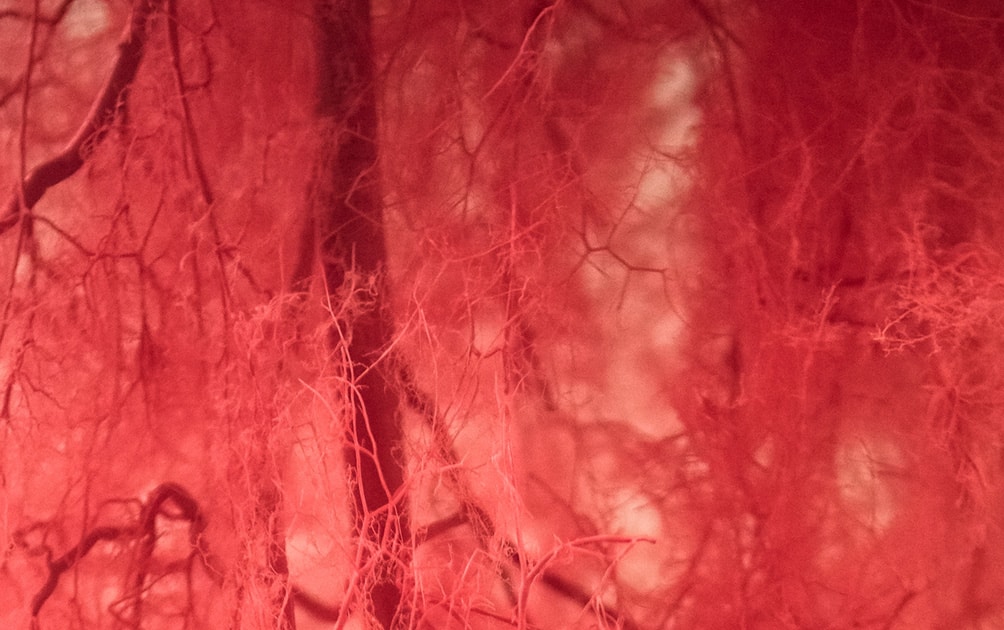

activities of daily living aging in place anemia arteries athletic performance BDNF blood blood doping blood flow blood flow modification blood vessel capillaries circulatory system Dr. Deepsea EPO erythropoiesis erythropoietin exercise hyperemia golf hydrocephalus hyperemia KAATSU for Business kaatsu japan kumamoto kumamoto castle Louis Chartier Nitric Oxide reactive hyperemia reactive hypermia red blood cell production rehab Rehabilitation sarcopenia senior fitness shear force Traumatic Brain Injury Using KAATSU vasoconstriction vasodilation VEGF veins venous flow vo2 max Walking